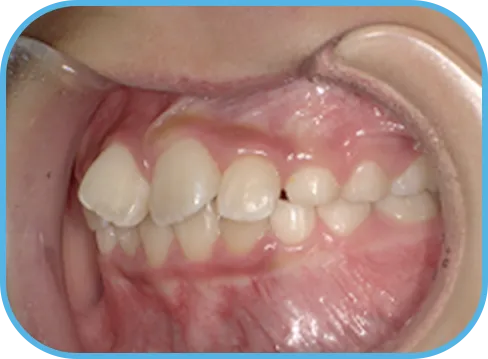

• Before

• 右 側

治療前右側からの歯の様子

• After

治療後右側からの歯の様子

主 訴

前歯ガタガタ、前歯が大きい

治療内容

インビザライン・ファースト

治療期間

7か月

治療費(税別)

450,000円+診断料5,000円

リスク・副作用

• 親知らずの影響や加齢などによって、凸凹が生じる可能性があります。

• 治療の初期段階では痛みや不快感が生じやすくなりますが、1週間前後で慣れます。

• 顎の成長発育によって、噛み合わせや歯並びが変化する可能性があります。

• 状況により当初予定した治療計画を変更する可能性があります。